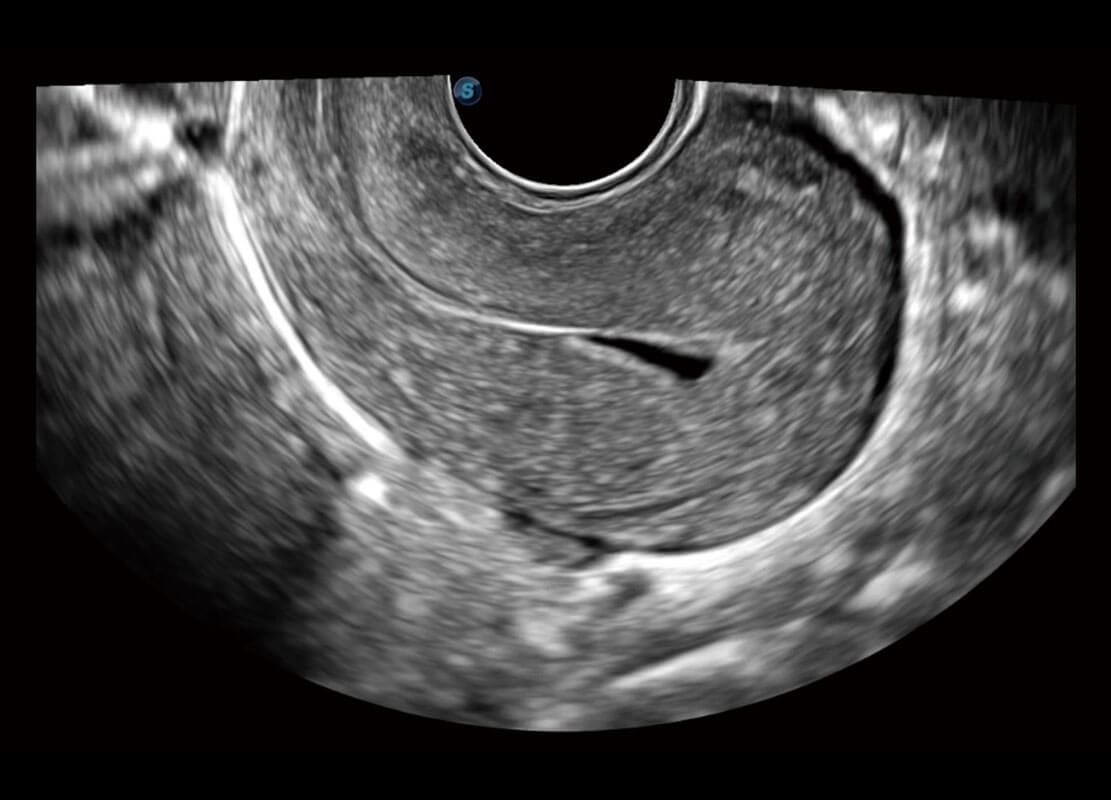

生殖健康

P60优异的图像质量搭载专科探头,在妇科基础疾病的诊断、卵泡生长的监测、输卵管通畅情况的判别等方面为您提供生殖应用方案。

• 腔内妇科-宫腔分离

• 腔内妇科-卵巢